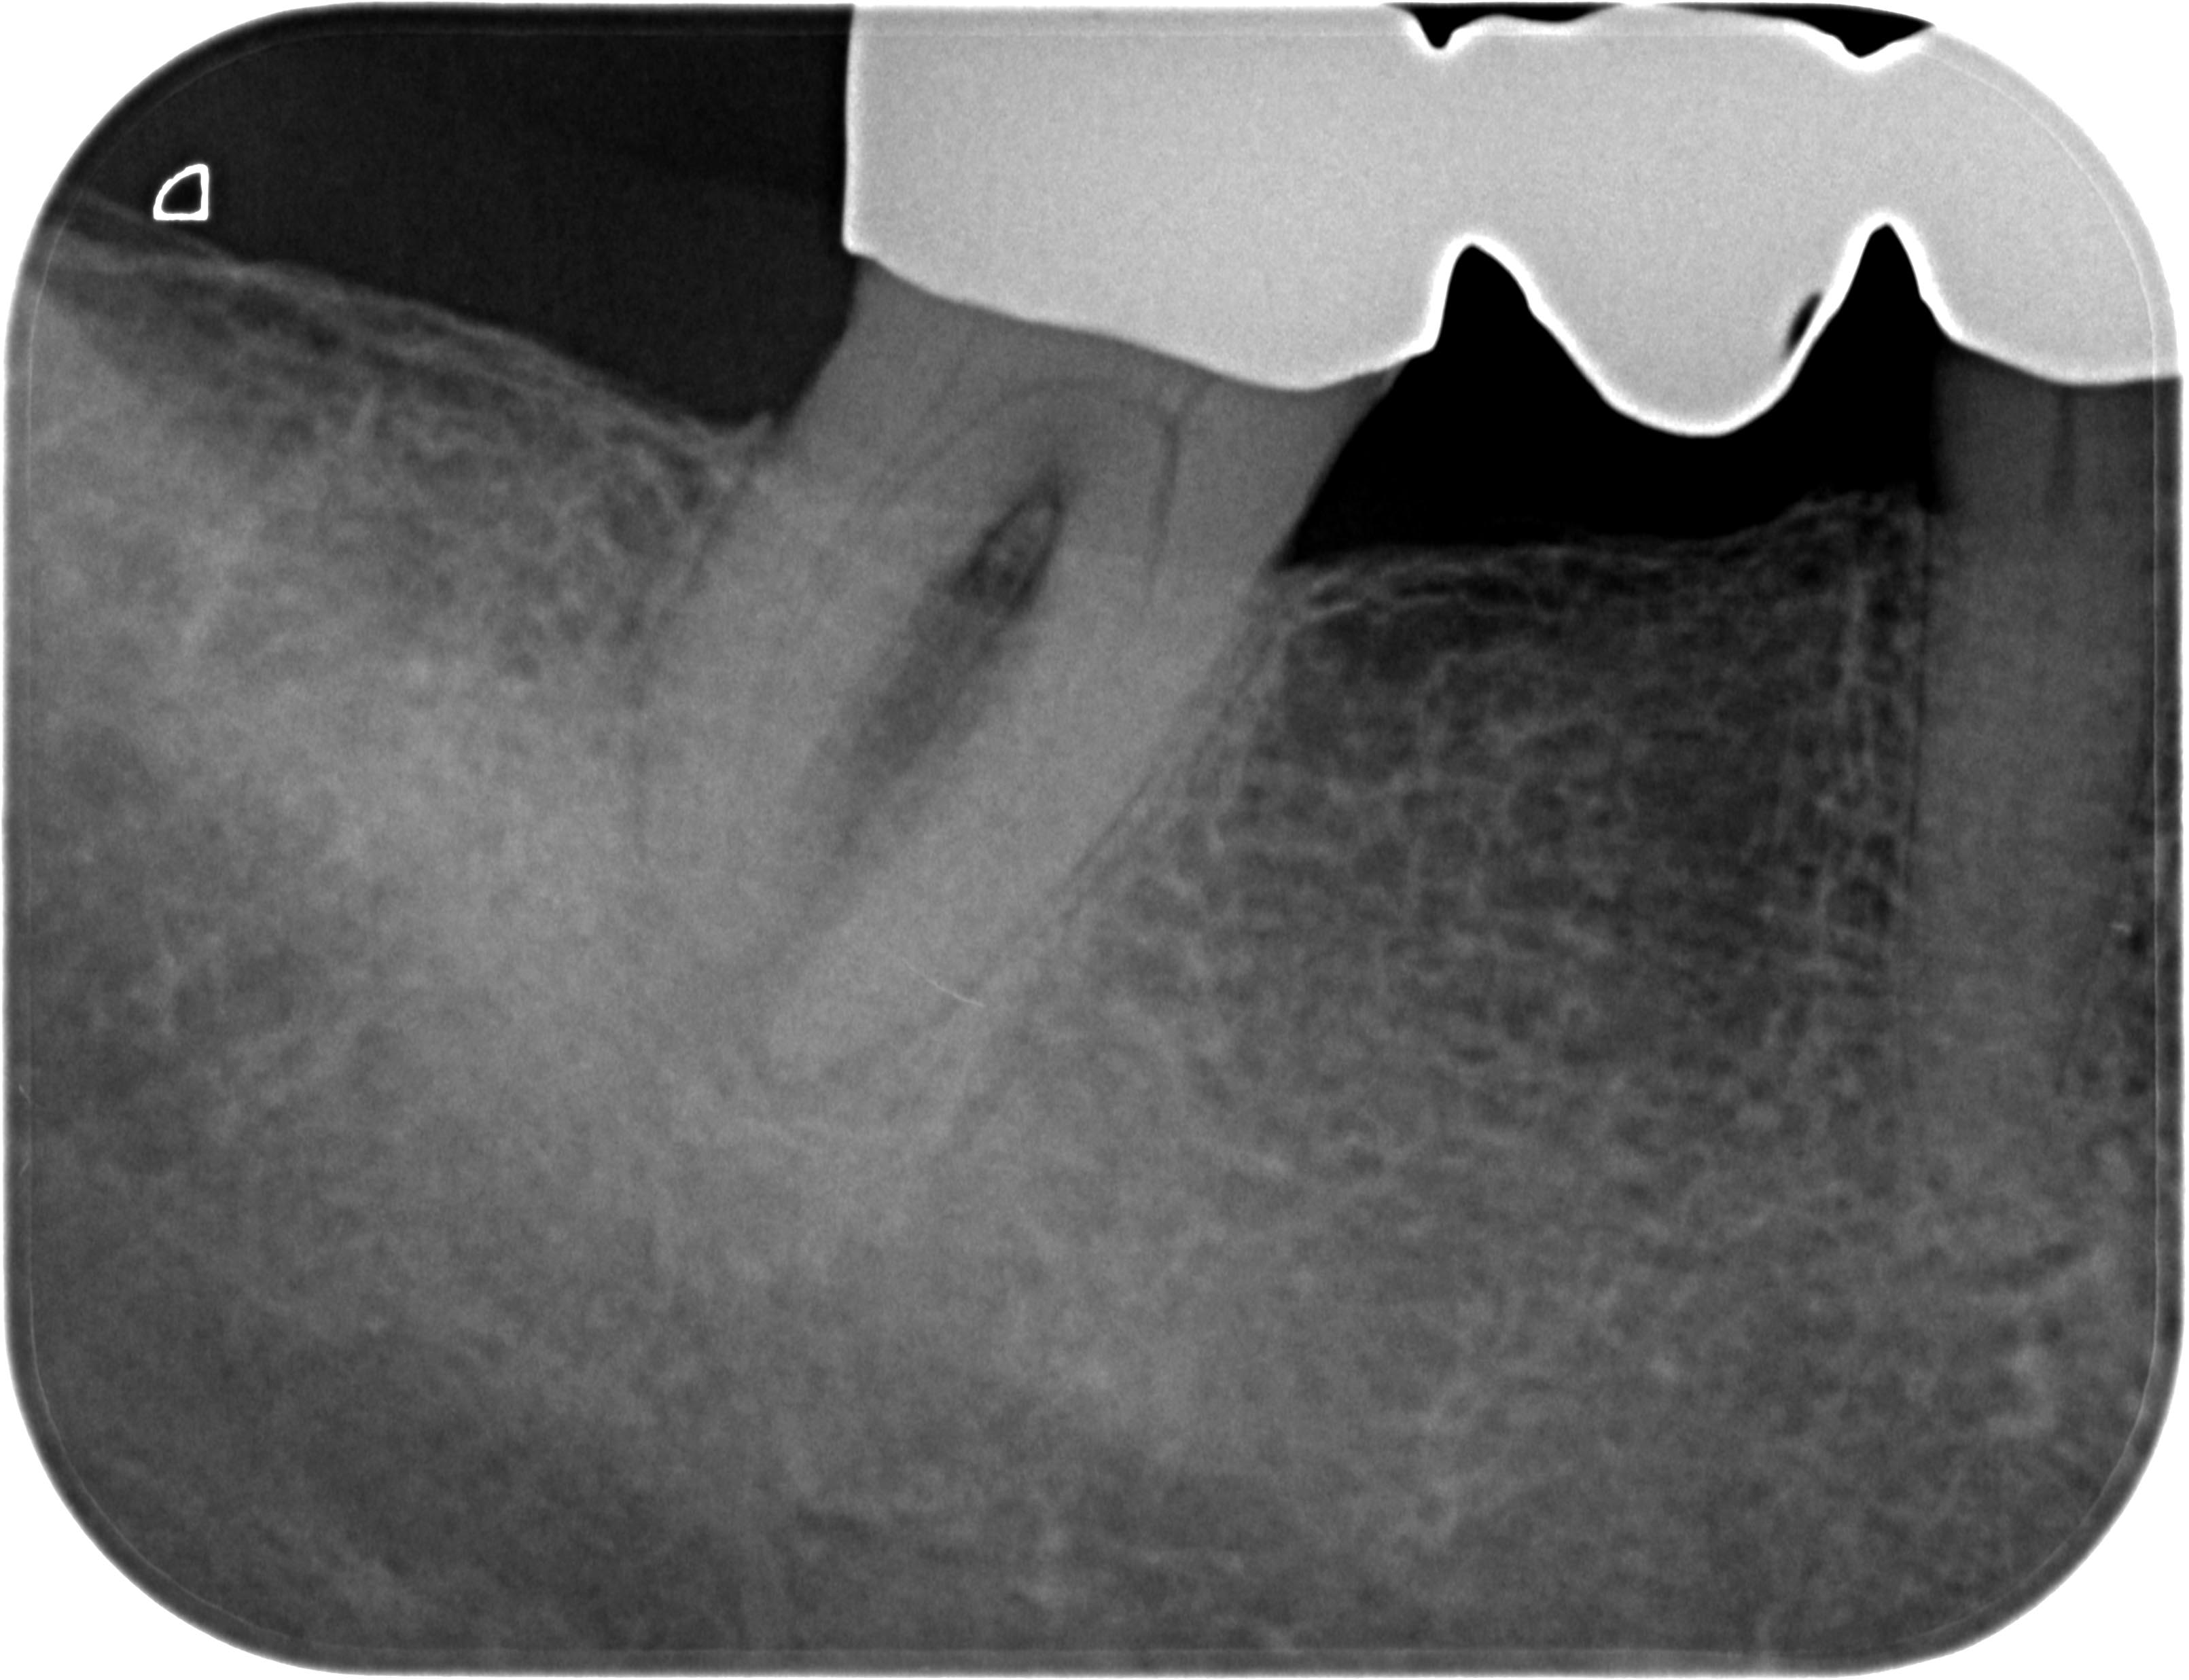

Resorption-1-4 Veröffentlicht 10. Juni 2013 am 3222 × 2473 in Was zeigt das DVT (4) ? Die Fälle Zahn 47